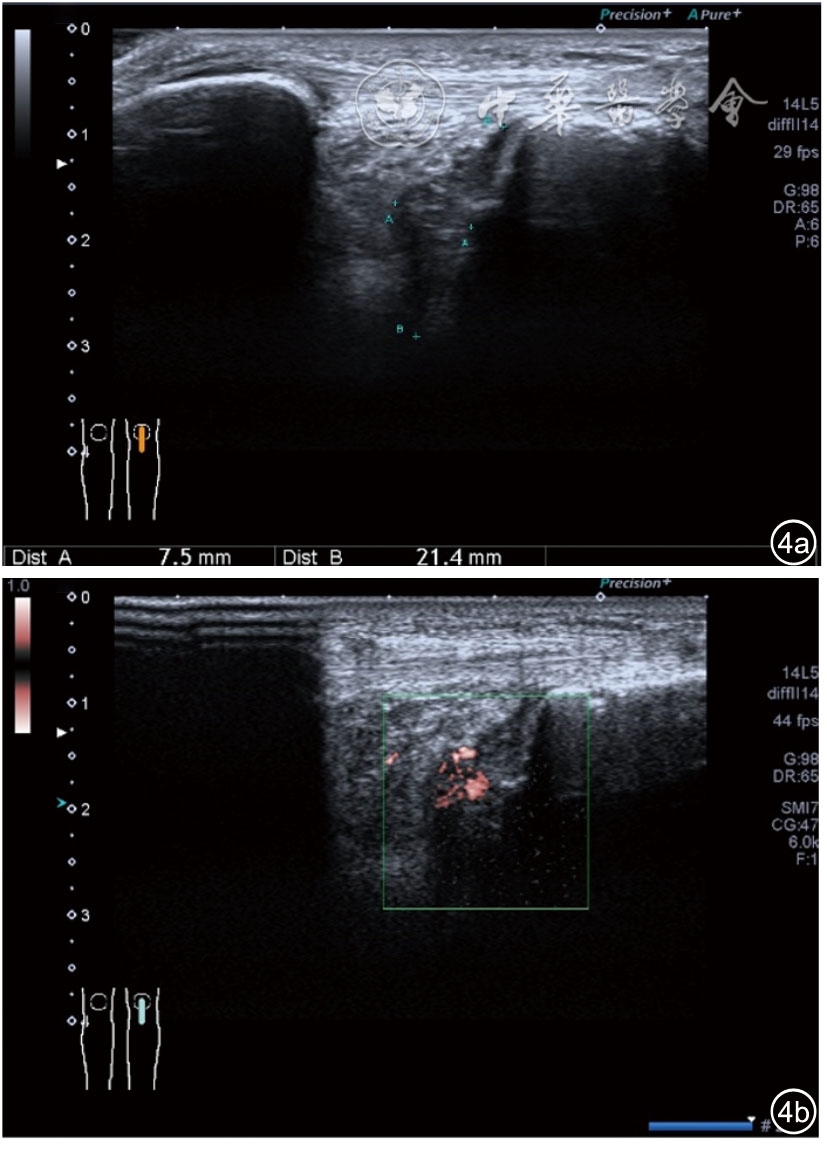

1.关节内表现。(1)骨改变。表现为骨末端或关节周缘出现的骨质局部突起改变,其后方伴或不伴有声影,多见于膝关节内侧缘和外侧缘(图1)。(2)软骨改变。股骨关节面改变可以在长轴及短轴切面显示,嘱患者屈曲膝关节,足平置于检查床,股骨滑车及股骨髁上半部分的关节面即可轻松显示。超声探查可见股骨负重面关节软骨发生不同程度的改变,轻者关节软骨浅侧边界模糊,重者可见关节软骨薄、缺失,软骨下骨缺损改变(图2)。(3)半月板外突。一般内侧半月板突出多见,外侧半月板突出比较少。半月板可见不同程度的外突,同时伴有膝内侧副韧带向外移位(图3)。半月板外周缘性滑脱是指半月板突出超出胫骨平台边缘的距离≥3 mm,其可引起一系列临床症状,早期诊断、早期治疗可以预防骨关节的进一步损伤。(4)交叉韧带损伤。可见前后交叉韧带增粗,回声减低(图4)。(5)髌上囊积液。膝关节是最容易发生积液的关节之一。患者仰卧位,关节积液最常见于膝关节上外侧,因为关节囊向髌股关节上外侧突出。髌上囊积液采用10~18 MHz的高频线阵探头于股四头肌腱纵断面及横断面扫查均可显示,探头频率取决于患者体型。超声可见低回声积液,慢性可伴有丛状滑膜增生(图5)。(6)脂肪垫水肿。脂肪垫在髌骨附着点处回声增强、增厚(图6)。

图4 交叉韧带损伤超声图像

2.膝关节静态结构治疗。动力平衡失调后,继发静态结构变化,出现内外侧副韧带、交叉韧带、脂肪垫、半月板等结构变化。这里介绍半月板与交叉韧带的处理。(1)膝关节静态结构半月板治疗。在膝关节骨关节炎中主要是突出和损伤。突出主要发生于膝内翻引起的内侧半月板突出,引起内侧副韧带的张力增高。内侧半月板与内侧副韧带相连,是引起膝关节内侧疼痛的主要原因之一。治疗主要是针刀剥离松解,部分损伤可行PRP注射。①半月板突出针刀剥离松解治疗。针刀治疗主要是松解和减压,缓解疼痛,不能复位。以内侧半月板突出治疗为例。患者平卧位,髋轻度外展外旋,膝关节屈曲30°,膝下垫一软枕。选用10 MHz超声探头,穿刺区域常规消毒,探头涂抹耦合剂后套入无菌手套碘伏消毒或使用无菌耦合剂。将探头置于患者皮肤表面,内侧关节间隙长轴扫查,找到半月板突出最高点,用25G针头,抽吸1%利多卡因3 ml逐层麻醉直到半月板。选用直径1 mm的Ⅰ型2号针刀从头侧向足侧方向在内侧副韧带与半月板之间,以及半月板内部进行剥离松解3~5刀拔出针刀(图13),局部压迫5分钟,无菌敷料覆盖。②半月板损伤PRP注射治疗。半月板损伤主要表现为髌下痛,伸膝加重,查体在髌下髌韧带与侧副韧带之间,沿关节间隙有固定或局限性压痛,伸膝过程中尤为明显。MRI可示半月板断裂、损伤。如果出现绞索,严重影响功能需手术治疗。半月板损伤治疗,以注射PRP修复为主。以内侧半月板后角损伤为例。患者俯卧位,治疗前准备同半月板突出针刀剥离松解治疗。选用25G注射针头,抽取1%利多卡因2 ml局部麻醉后,制取1.5 ml PRP,穿刺到达半月板撕裂处注射,注射完毕后出针(图14),局部压迫2分钟,无菌敷料覆盖。(2)膝关节静态结构交叉韧带治疗。膝关节骨关节炎交叉韧带损伤多为部分损伤,治疗早期主要为药物或PRP注射,效果不佳时针刀做止点松解。①后交叉韧带损伤药物注射治疗。主要治疗韧带肿胀、无明显断裂患者。患者俯卧位,膝关节伸直位。一般选用10 MHz超声探头,治疗前准备同半月板突出针刀剥离松解治疗。将探头置于患者皮肤表面,后交叉韧带长轴扫查,找到胫骨止点,选用22G长针头,抽吸1%利多卡因3 ml+曲安奈德10 mg,从头侧向足侧方向穿刺到后交叉韧带胫骨止点部位的韧带表面进行注射,注射结束拔出针头(图15),局部压迫2分钟,无菌敷料覆盖。②前交叉韧带损伤PRP注射治疗。患者仰卧位,膝关节伸直。选用10 MHz超声探头,治疗前准备同半月板突出针刀剥离松解治疗。将探头置于患者皮肤表面,短轴扫查,找到前交叉韧带胫骨止点,选用25G针头,抽吸1%利多卡因3 ml逐层麻醉直到韧带止点部位,制备PRP 3 ml注射到前交叉韧带显露部位,注射结束拔出针头(图16),局部压迫2分钟,无菌敷料覆盖。③前交叉韧带损伤针刀剥离松解治疗。体位与治疗前准备同前交叉韧带损伤PRP注射治疗。短轴扫查找到前交叉韧带胫骨止点,选用25G针头,抽吸1%利多卡因3 ml逐层麻醉直到韧带止点部位,选用直径0.6 mm的Ⅰ型2号针刀从外侧向内侧于前交叉韧带胫骨止点部位剥离松解3~5刀拔出针刀(图17),局部压迫5分钟,无菌敷料覆盖。